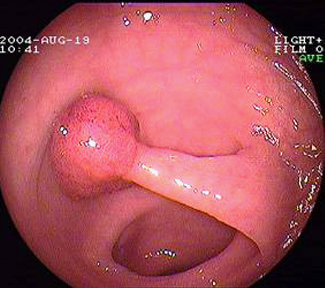

In den meisten Fällen entwickelt sich ein Darmkrebs aus einem zunächst gutartigen Dickdarmpolypen, auch Adenom genannt. Bei 10% der Darmkrebsfälle sind genetische Faktoren beteiligt, welche die Entstehung eines Krebses begünstigen.

Bei Verdacht auf Darmkrebs untersucht der Arzt zunächst den Stuhl auf verborgenes Blut (okkultes Blut) und tastet den Enddarm aus. Auch bei fehlendem Blutnachweis im Stuhltest und normalem Befund der Tastuntersuchung des Mastdarms ist bei weiter bestehendem Verdacht eine Darmspiegelung (Koloskopie) angesagt.